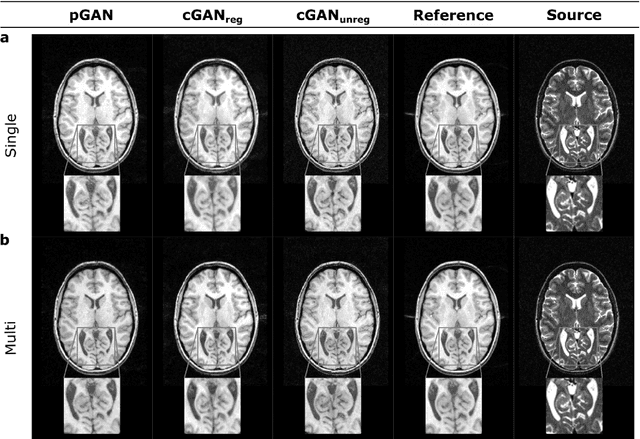

Abstract:Acquiring images of the same anatomy with multiple different contrasts increases the diversity of diagnostic information available in an MR exam. Yet, scan time limitations may prohibit acquisition of certain contrasts, and images for some contrast may be corrupted by noise and artifacts. In such cases, the ability to synthesize unacquired or corrupted contrasts from remaining contrasts can improve diagnostic utility. For multi-contrast synthesis, current methods learn a nonlinear intensity transformation between the source and target images, either via nonlinear regression or deterministic neural networks. These methods can in turn suffer from loss of high-spatial-frequency information in synthesized images. Here we propose a new approach for multi-contrast MRI synthesis based on conditional generative adversarial networks. The proposed approach preserves high-frequency details via an adversarial loss; and it offers enhanced synthesis performance via a pixel-wise loss for registered multi-contrast images and a cycle-consistency loss for unregistered images. Information from neighboring cross-sections are utilized to further improved synthesis quality. Demonstrations on T1- and T2-weighted images from healthy subjects and patients clearly indicate the superior performance of the proposed approach compared to previous state-of-the-art methods. Our synthesis approach can help improve quality and versatility of multi-contrast MRI exams without the need for prolonged examinations.